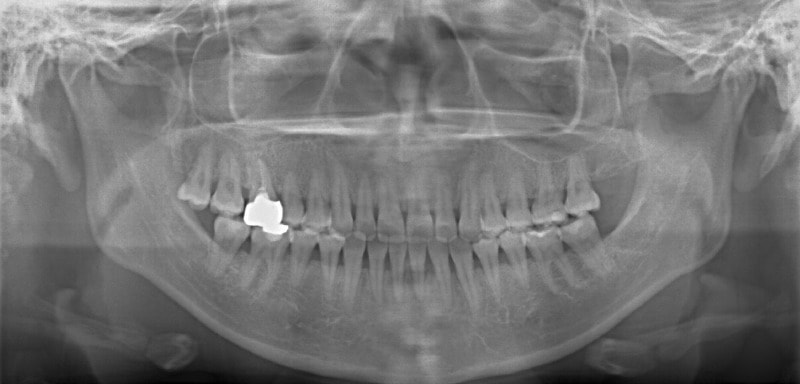

治療後パノラマレントゲン

歯根のパラレリングは良好です。顎関節に問題はありません。